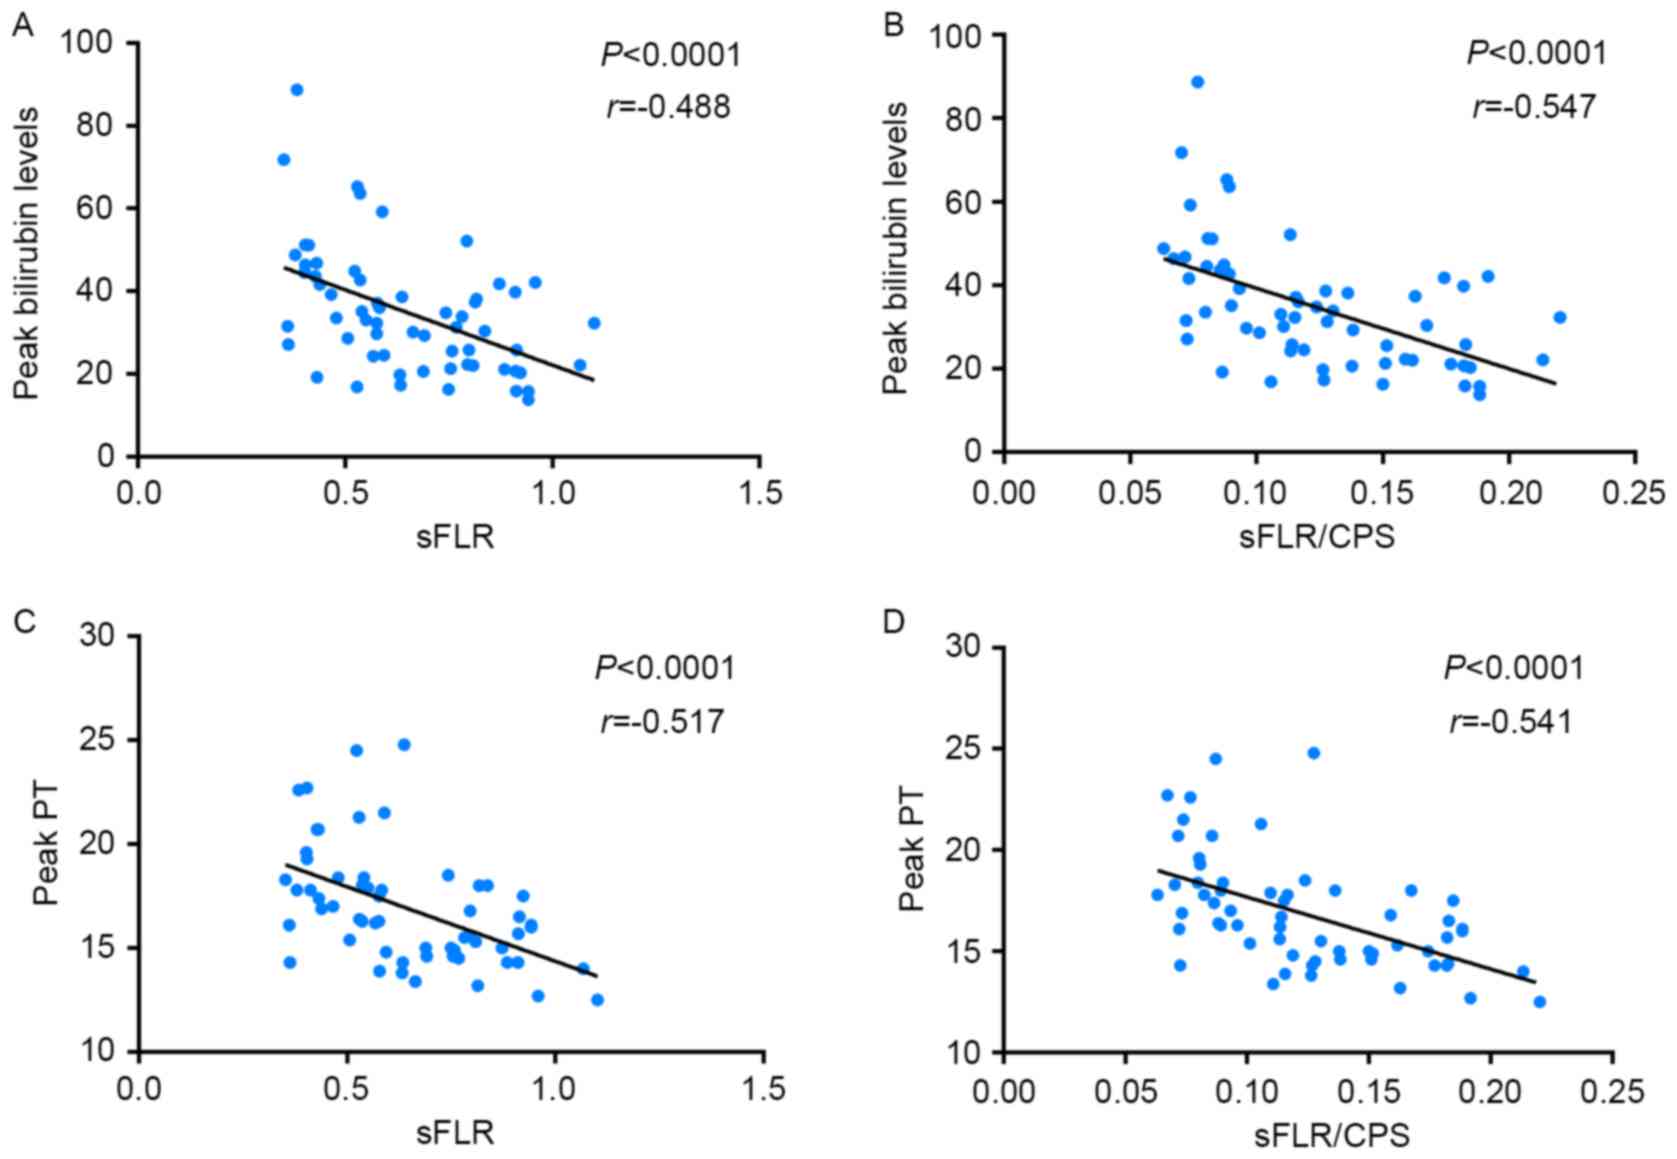

Pearson's correlation analysis revealed that the

postoperative peak bilirubin level had a stronger negative

correlation with sFLR/CPS (P<0.0001, r=−0.547) than with sFLR

(P<0.0001, r=−0.488) (Fig. 2). The

postoperative peak PT had a stronger negative correlation with

sFLR/CPS (P<0.0001, r=−0.541) than with sFLR (P<0.0001,

r=−0.517) (Fig. 2).